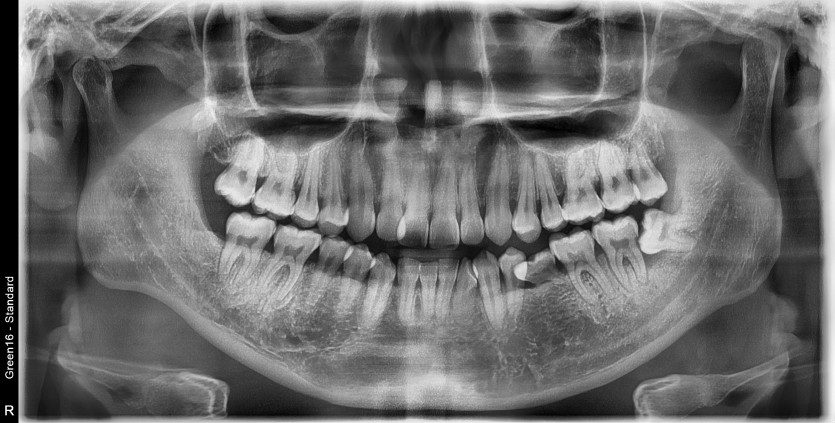

#28,38 사랑니 발치

구강 외과 전문의가 당일 발치했습니다.